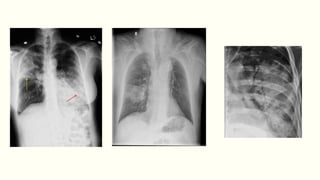

Chest X-ray

Lobar pneumonia

ļ‚§Patchy opacification evolves into homogeneous consolidation

of affected lobe

ļ‚§Air bronchogram (air-filled bronchi appear lucent against

consolidated lung tissue) may be present.

Bronchopneumonia: Typically patchy and segmental shadowing

Complications: Para-pneumonic effusion, intrapulmonary

abscess or empyema

Staph.aureus: Suggested by multilobar shadowing, cavitation,

pneumatocoeles and abscesses